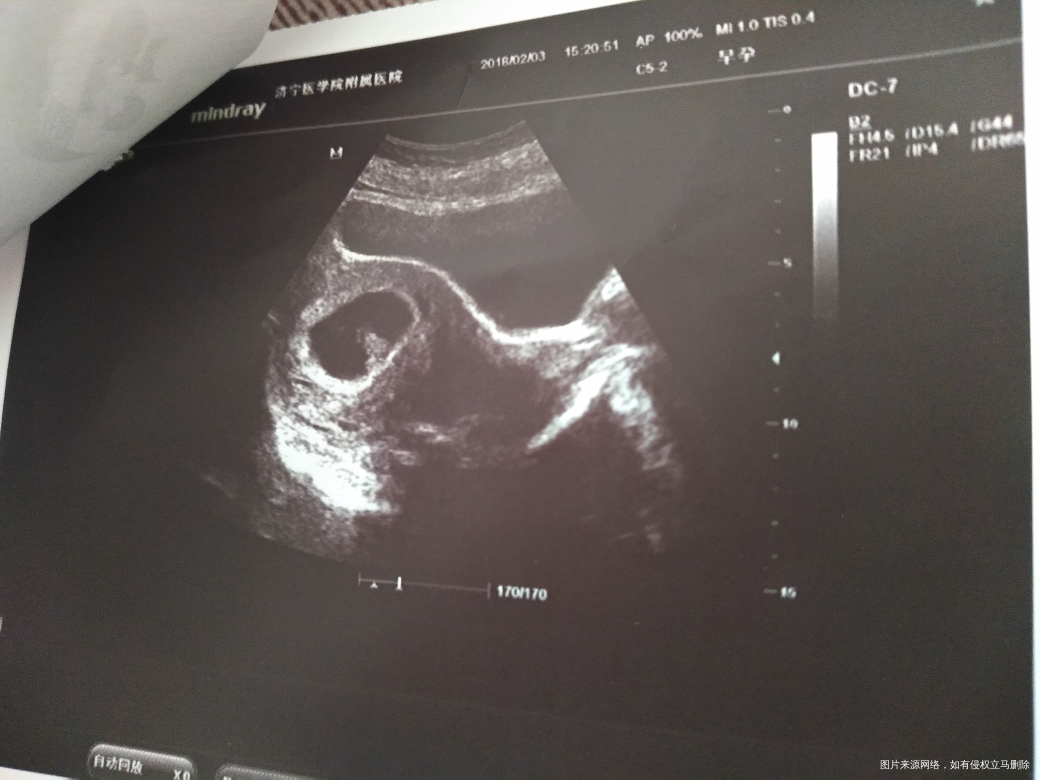

58天又流血了,今天又做了B超,请医生帮忙看看B超怎么样?

你好,胚胎发育正常,继续保胎治疗,卧床休息。

b超显示发育正常,卧床休息,保胎治疗。如果我的回答对您有所帮助,请采纳。

B超提示胚胎发育正常,建议绝对卧床休息,药物保胎

B超显示胎儿发育挺好的,建议卧床休息,好好保胎。